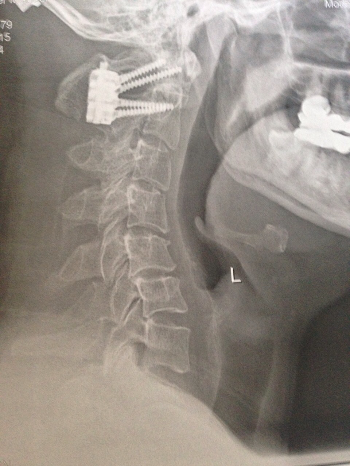

Ich bin 46 Jahre alt nach 3 Operation mit Versteifung habe ich jetzt ein Problem. ein Stab ist gebrochen. sieht man auch gut auf dem Bild .

das heißt bricht der andere auch dann war es das dass heißt GenikBruch und das war es dann

1 Stab von 2 Stäben ist mir im Nacken gebrochen ,obwohl das Titan ist , und alle sagen das bricht nicht (((((ein Bild davon können sie sich anschauen , das heißt einmal hinfallen und das war es ,dannnnn.